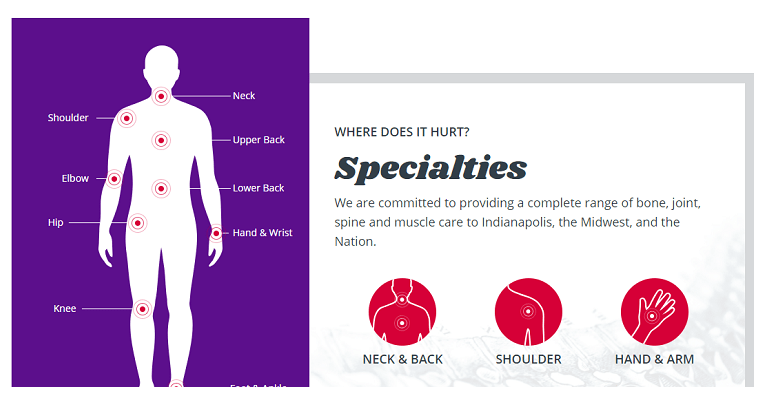

廣告醫療服務或醫療產品銷售網站的正確內部結構是該項目成功的基礎。對于SEO來說也很重要,因為所有頁面的正確結構將導致目標用戶。語義,類別和子類別的定義的主管選擇(這是用于醫療門戶尤其重要),選擇合適的類型的結構保證從用戶的角度來看的便利性。

在調整導航時,類別和子類別的名稱應與潛在客戶正在尋找的名稱相匹配。例如,如果一家醫院提供了半月板縫合服務,并且用戶搜索了半月板損傷治療,則應該以這種方式命名類別和服務。

功能性

對于醫學網站而言,考慮和開發特殊功能非常重要。有了它的幫助,不僅可以吸引,激勵和執行訪客的行動,而且還可以大大簡化工作人員的工作。

網站的功能和能力類型直接取決于其主題。例如,對于醫療中心而言,一個很好的解決方案是建立一個個人帳戶,客戶可以在其中查看就診,推薦和醫生約會的記錄。在專門用于診所的美國醫療網站上,在線約會系統非常發達。訪客只需選擇醫生,方便就診的日期和時間。同時,這種系統形成了醫生的空閑時間以進行預約。這極大地簡化了工作人員的工作,他們只需要打電話給客戶并闡明數據的準確性。 對于醫療門戶網站,功能將完全不同,并且取決于其方向。在這里,有必要關注便利性,實施正確的聚合器,按名稱,制造商分類的搜索系統。在網上商店集中銷售蜂蜜。藥品或設備,最重要的是產品卡,在該產品卡上必須放置其銷售結構的典型主要功能。 |